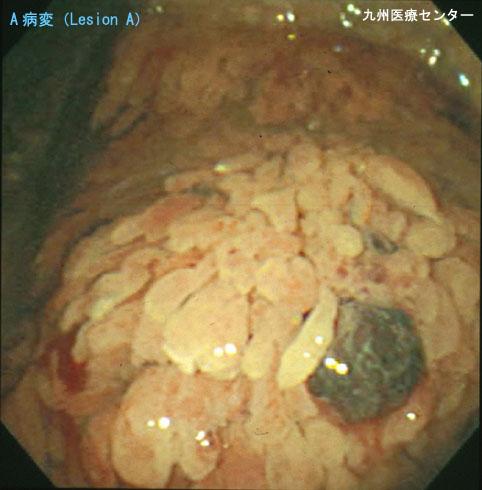

A case of villous tumor of the stomach with diodenal adenoma.

Fukuoka Pref., National Hospital Organization Kyushu Medical Center

Location

Stomach/Body

Technique, Method

Endoscopy

Macroscopic Types

Type 0/Others

Size

40 -

Depth of Tumor Invasion

mucosa